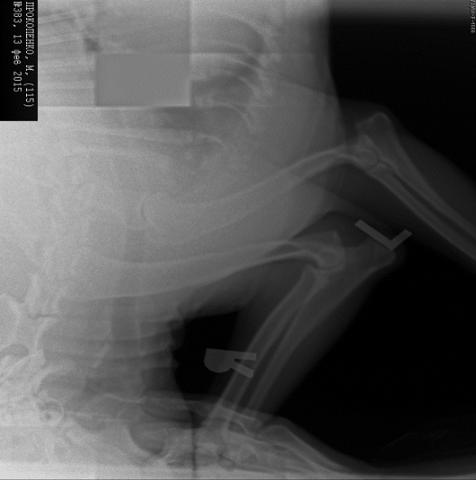

Здравствуйте! У меня амстафф девочка 11 месяцев. На основании данного рентгеновского снимка нам поставили диагноз "Дисплазия локтевого сустава" правой передней лапы. Прилагаю снимок и очень прошу высказать свое мнение. Заранее благодарю!